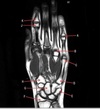

6

Q

What is letter D?

A

SUPRASPINATUS MUSCLE

How well did you know this?

1

Not at all

2

3

4

5

Perfectly

7

What is letter A?